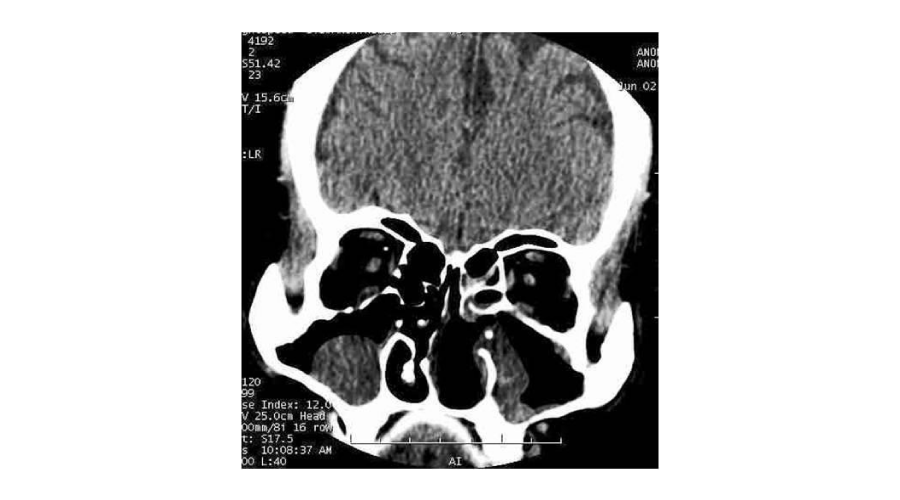

CT scan of nose and PNS revealed destruction of turbinates and that of cartilaginous and bony septum (Figure 3). Biopsy from nasal tissue showed plasma cell infiltrate with evidence of endarteritis (Figure 4). The patient was evaluated as a case of Secondary atrophic rhinitis with the goal to arrive at the etiology. Blood counts, liver functional tests, renal function test, routine and microscopic examination of urine, Mantoux test, chest radiograph were normal.

Figure 3: